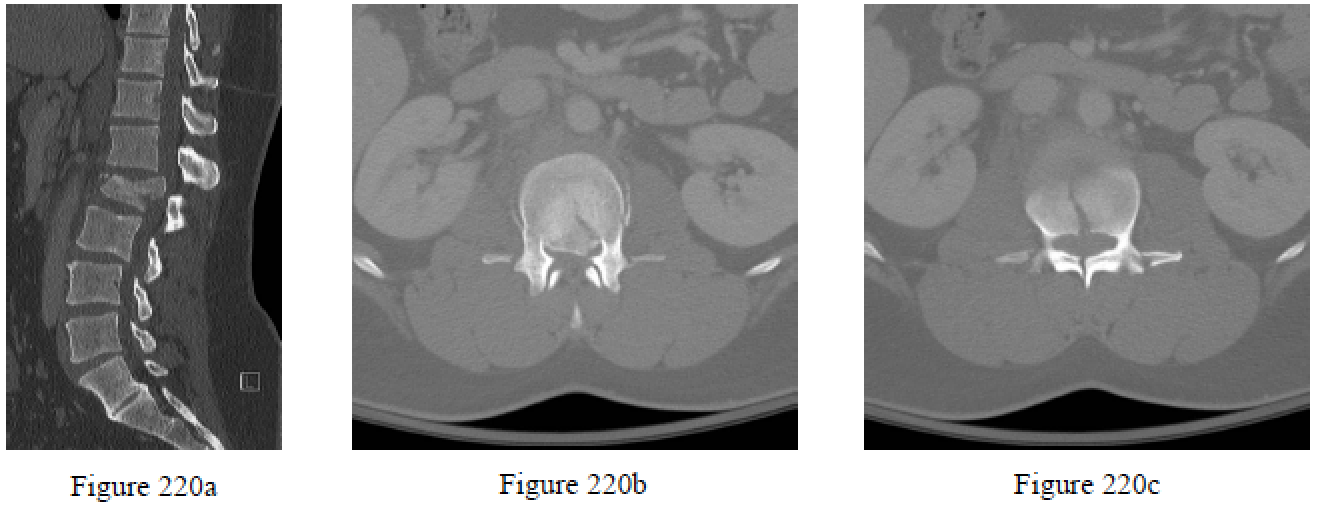

Question 220

Figures 220a through 220c are the CT scans of a 35-year-old man who is seen after a motor vehicle collision. Examination reveals weakness in ankle dorsflexion (3/5) and bilateral ankle plantar flexion (1/5). He has decreased sensation in the perineal region and absent rectal tone. What is the most appropriate treatment?